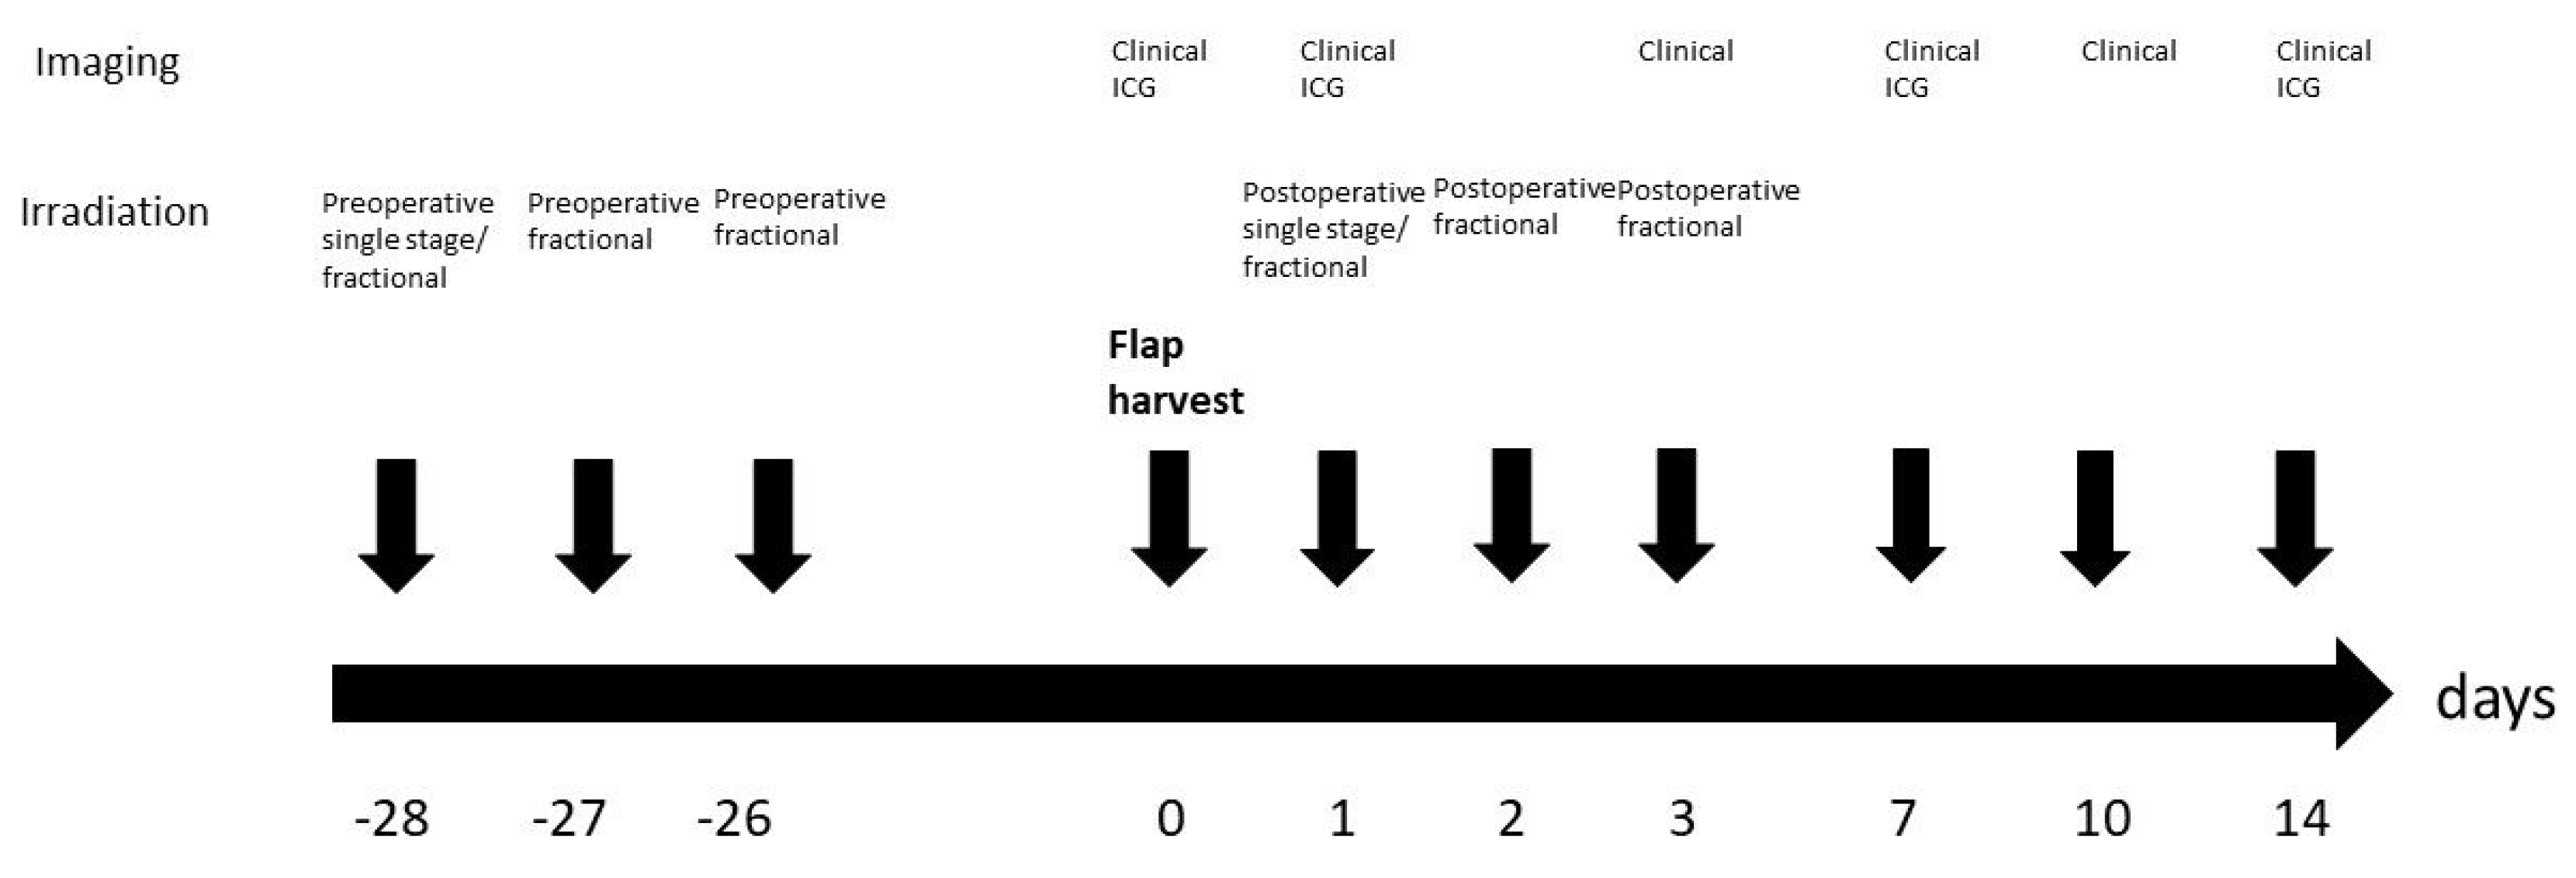

2.2. Irradiation Procedure

2.3. Groups

2.4. Imaging